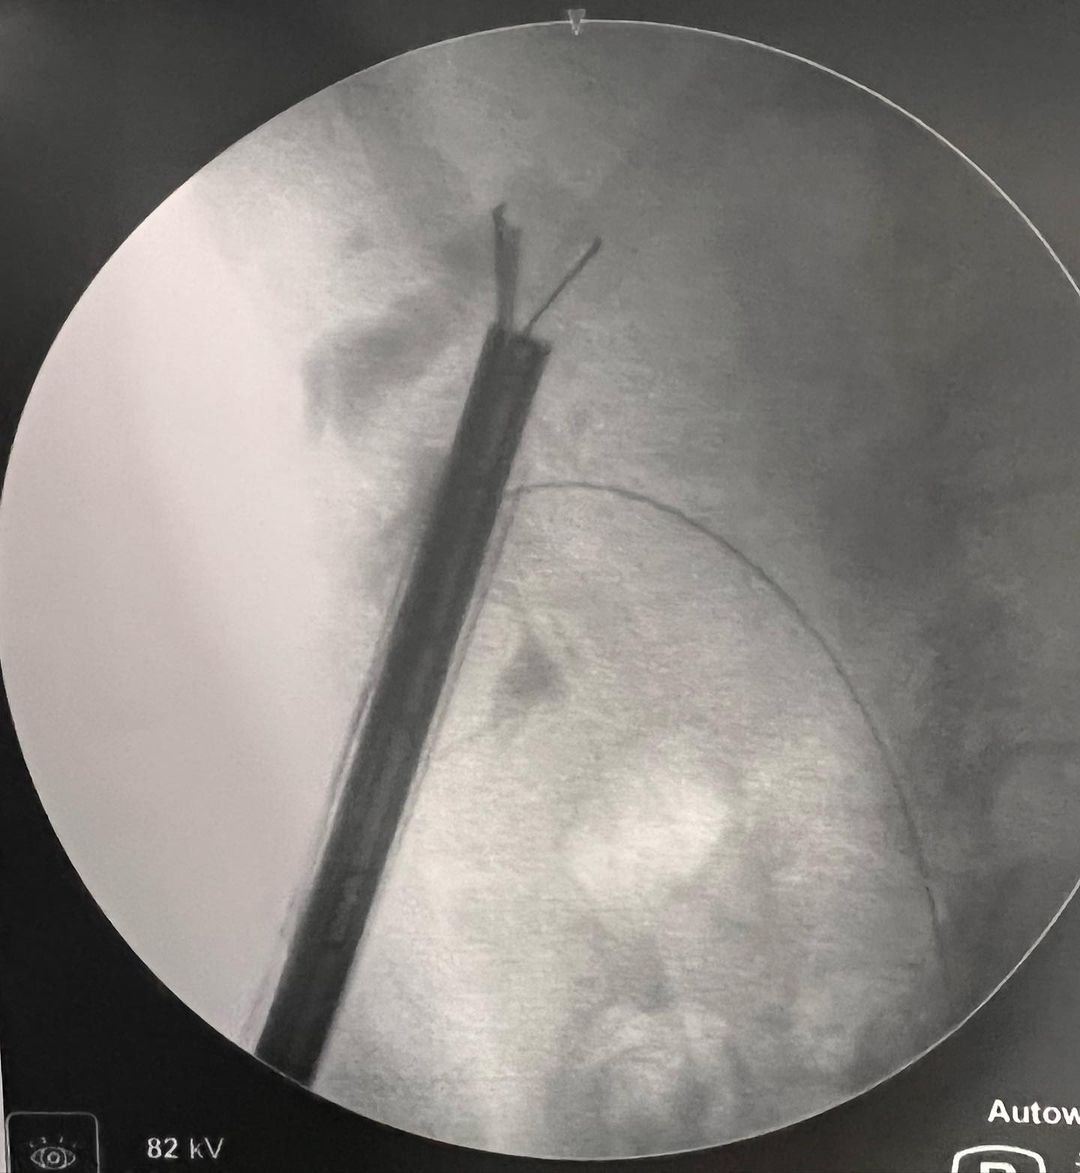

Especialista em Cirurgias Urológicas Minimamente Invasivas, com destaque para Cálculos Renais e Tumores Urológicos.

Imagens